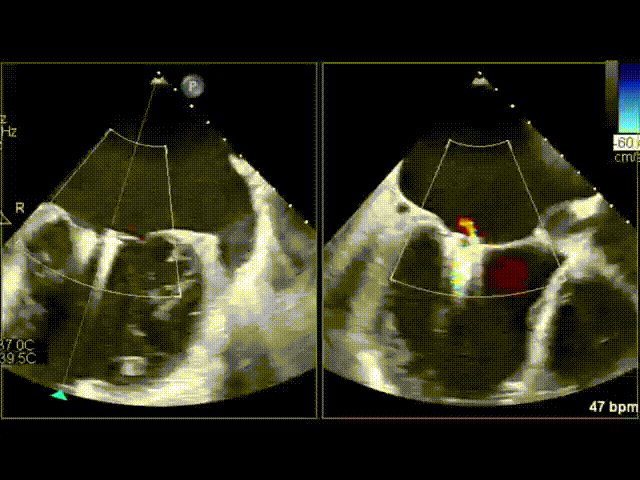

术中通过食道超声再次确认患者二尖瓣反流主要在2区,同时也累及1区和3区,反流极重度(+++++),反流口面积达到8*19mm,单夹无法有效解决反流问题。魏来教授临时改变手术方案,决定先在相对困难的3区尝试夹合,然后在2区平行释放第二个夹子。术中魏教授在心脏超声室潘翠珍教授、李伟教授鼎力配合下,通过娴熟的技术,完美达成了术前的既定方案,术后食道超声提示二尖瓣仅轻度反流(+),平均压差仅3mmHg。魏教授和李伟教授均连声感慨:“出乎意料,手术效果超过预期。”

3区释放第一个夹合器后该区反流消失

2区释放第二个夹合器后反流从极重度减少到轻度

该手术心脏操作仅30分钟不到,整台手术仅用时1小时,术后切口仅4cm(两指),真正做到了微创、高效、快捷,也为心外科医生处理这类疑难病例提供了一种行之有效的方案。